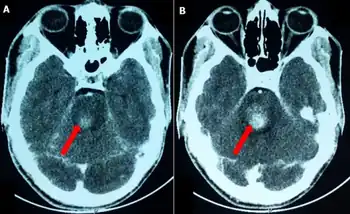

Foville's syndrome is caused by the blockage of the perforating branches of the basilar artery in the region of the brainstem known as the pons.[1] It is most frequently caused by vascular disease or tumors involving the dorsal pons.

Structures affected by the infarct are the dorsal pons(pontine tegmentum) which comprises paramedian pontine reticular formation (PPRF), nuclei of cranial nerves VI and VII, corticospinal tract, medial lemniscus, and the medial longitudinal fasciculus. There is involvement of the fifth to eighth cranial nerves, central sympathetic fibres (Horner syndrome) and horizontal gaze palsy.